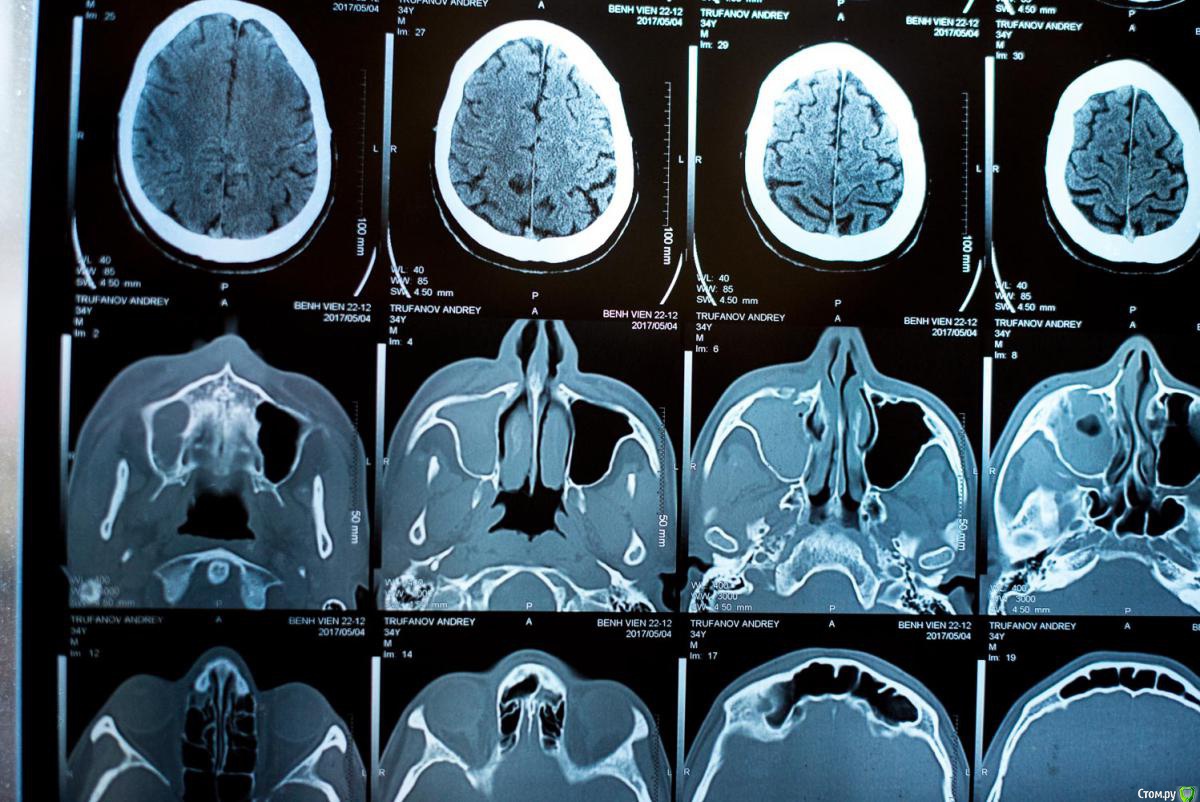

andrei_trufanov Опубликовано 4 мая, 2017 Поделиться Опубликовано 4 мая, 2017 Добрый день ! Требуется Ваш помощь, обратиться больше некуда , ситуация такая нахожусь сейчас длительное время во Вьетнаме, 1мая получил травму лица , сегодня был у лора ,сделал КТ, врач сказал что перелом лицевой кости и воспаление и что операцию делать не нужно или он не могут, не совсем понял , назначил лекарства и просил прийти через 10 дней. Подскажите на сколько серьезна ситуация нужна ли операция если да , то как срочно и правильны ли назначены лекарства ? Augmentin BD 1000mgAlpha chymotrypsin (AL-KIISIN)Methyl prednisolon 16mg(Medrol)Mequitazine 5mg(ITAMETAZIN)Acetylcystein 200mg(ACEMUC 200)Otrivin 0.1% Nosal Spray 10mlBudesonide 64mcg (BENITA) Ссылка на комментарий

St. Опубликовано 4 мая, 2017 Поделиться Опубликовано 4 мая, 2017 Перелом есть. Воспаление в гайморовой пазухе по снимку тоже есть. Так что с диагостикой все верно. 2 Ссылка на комментарий

ПалСаныч Опубликовано 4 мая, 2017 Поделиться Опубликовано 4 мая, 2017 Лично мое мнение: перелом есть. Смещение небольшое. В пазухе кровь. Если рот открывается в полном объеме, нет двоения в глазах и под глазом пальцем не ощущается костной ступеньки, то и жить спокойно дальше. Из назначенного оставил бы аугметин и спрей в нос. 6 Ссылка на комментарий

Irouil Опубликовано 4 мая, 2017 Поделиться Опубликовано 4 мая, 2017 Рот открывается? Если да, то спим на другой стороне и все. Больше ничего делать на данный момент не требуется, воспаления нет, в пазухе кровяка, смещение выглядит минимальным. Период бережливого отношения к лицу - месяц, потом можете еще раз ломать)) Аугментин допивайте, я бы еще антигистаминные назначил - лоратадин/дезлоратадин по 1-2 в сутки или цетиризин/супрастин на ночь по таблетке, ну и спрей, да. Вообще я почти во всем тут с Павлом Александровичем согласен. Ссылка на комментарий